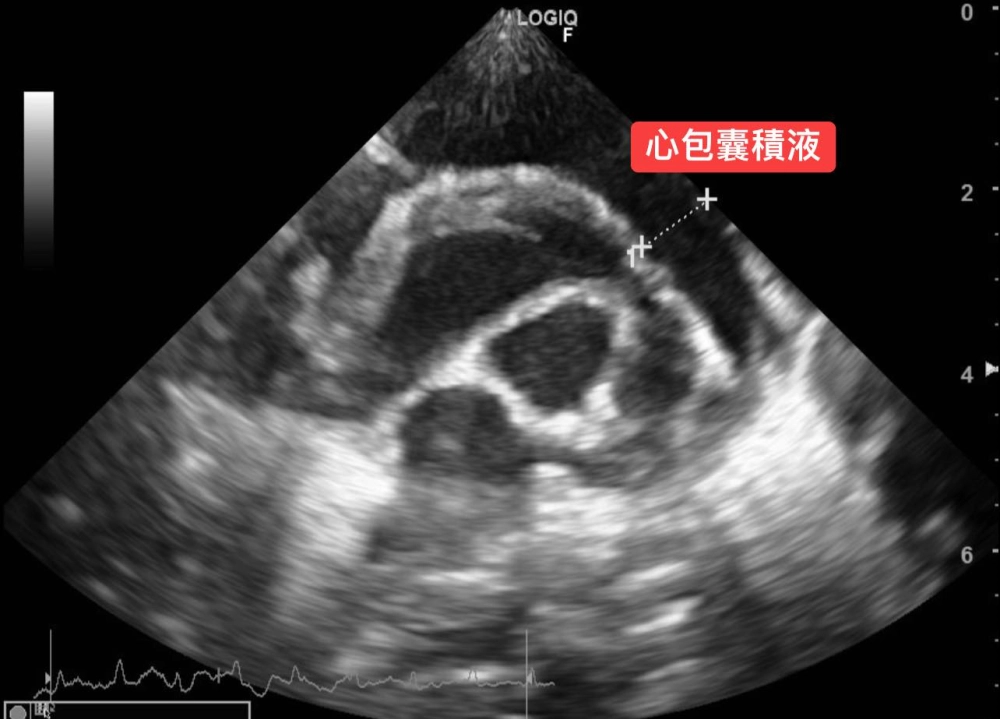

3. 心臟超音波檢查發現「大量心包囊積液」。

可見心臟周圍充滿心包囊積液